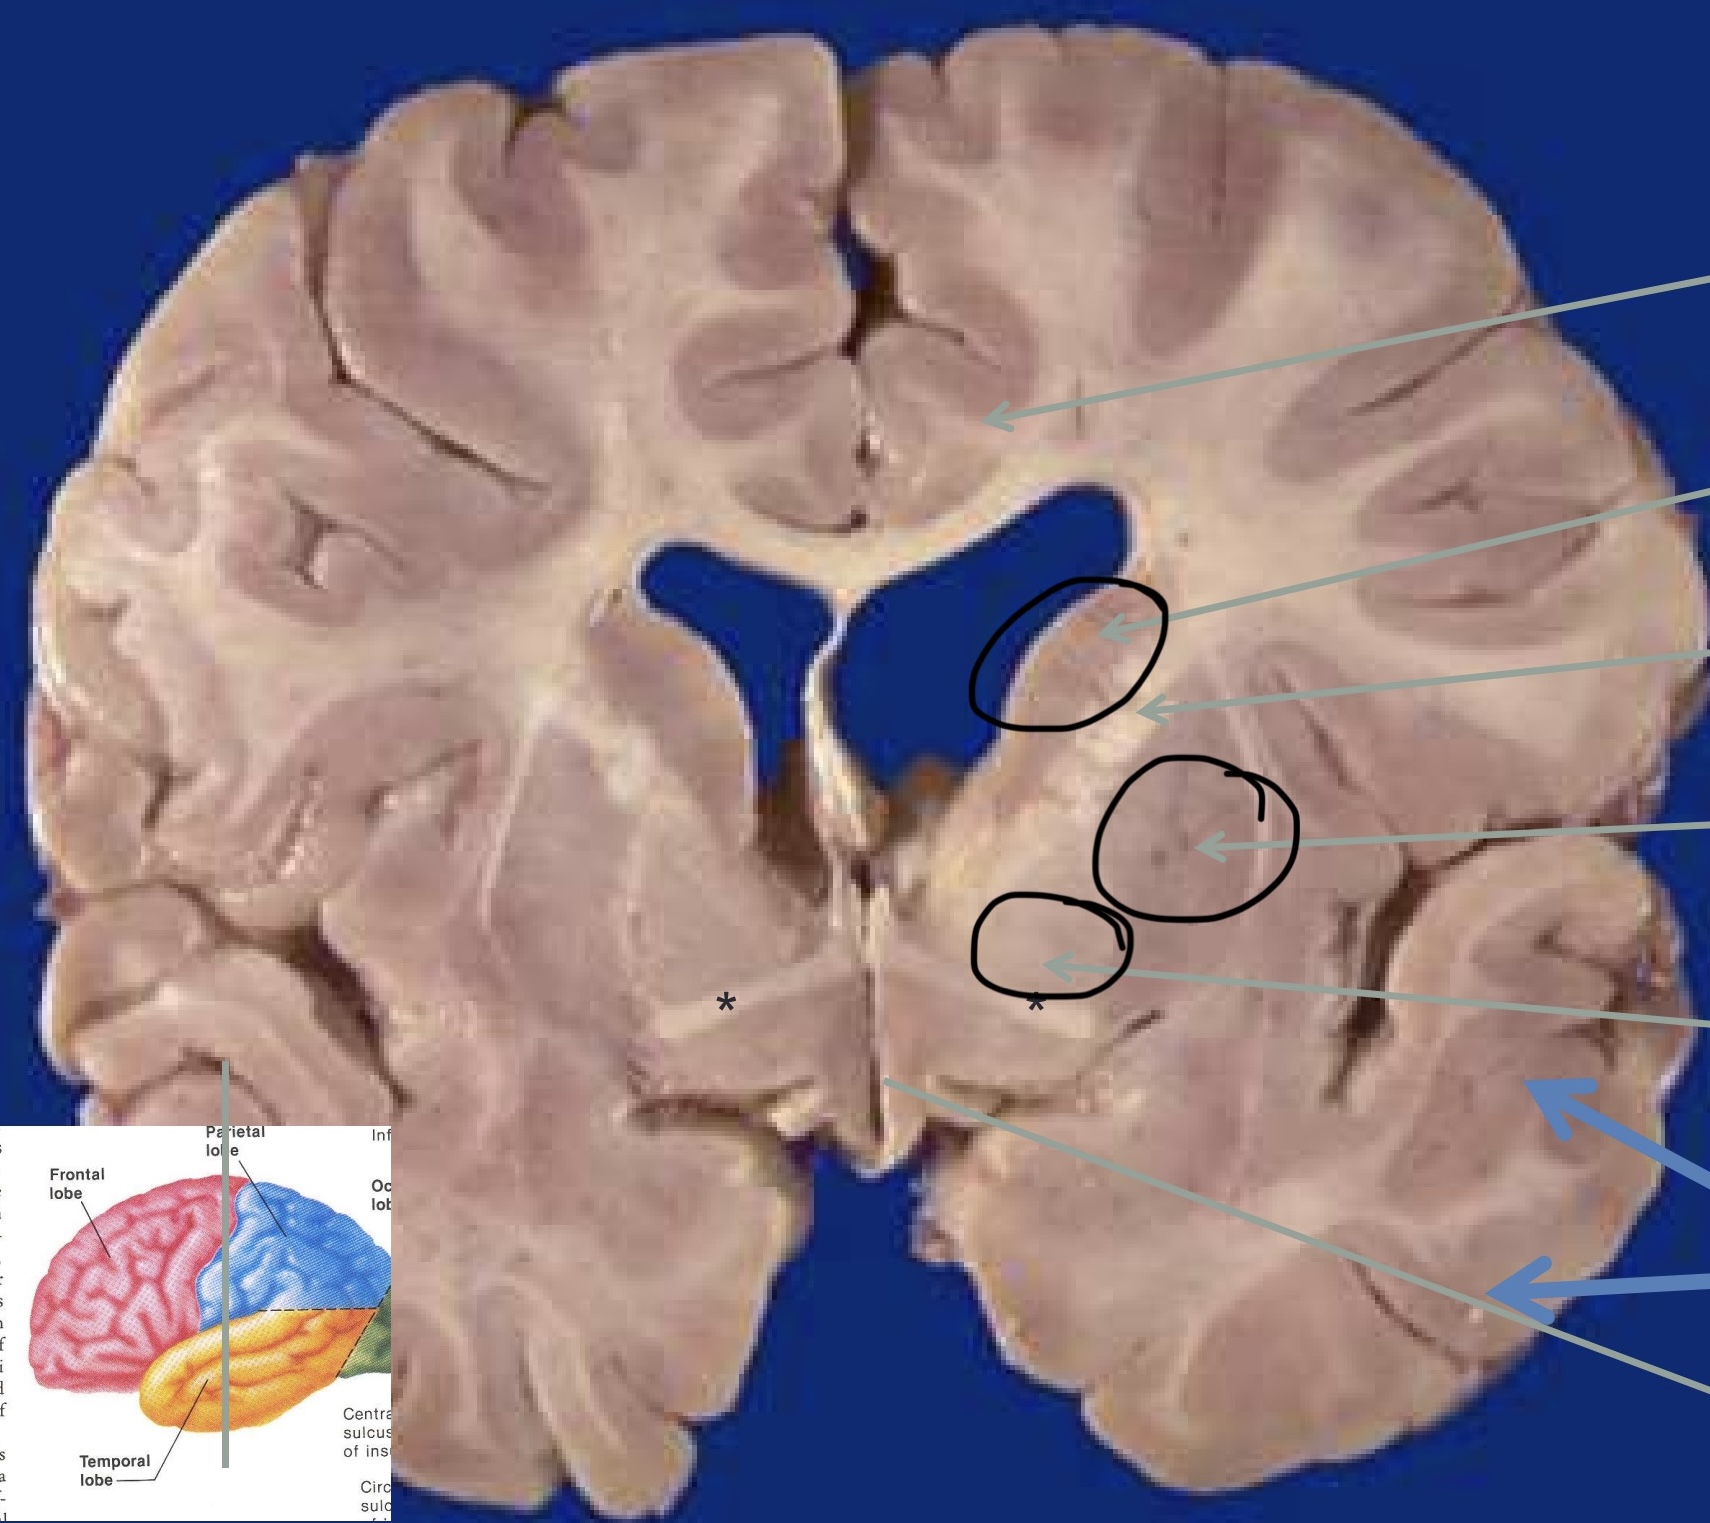

Identifiez la matière grise et la matière blanche

Orange = matière grise

Noir = matière blanche

Qu’est ce que le corps calleux ?

Substance blanche avec des axones qui relient les deux hémisphères

Que sont les noyaux gris ?

Noyau caudé, globus pallidus et putamen

Permettent une motricité involontaire, du tonus musculaire et une activité motrice

Qu’est ce que le diencéphale ?

Comprend le thalamus, l’épithalamus et l’ypothalamus